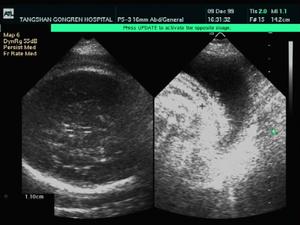

胎兒水腫應在產前即作出診斷,可從B超測出胎兒皮膚厚度,如≥5mm或有胎盤增大、漿膜腔積液,可得出初步診斷。也可通過B超發現心臟畸形,或通過羊水檢查胎兒血型、免疫物質、膽紅素、染色體核型或DNA以及血紅蛋白電泳等,有助於病因的診斷和治療。根據病史、症狀、體徵及血尿化驗等可對新生兒水腫的病因做出診斷。對某些罕見的病因則需進一步行特殊的免疫、內分泌、染色體檢查。

2.心電圖及超聲心動圖 對診斷心肌病變有幫助,特別是二維超聲心動圖可動態觀察心臟功能、房室大小和壁的厚薄。